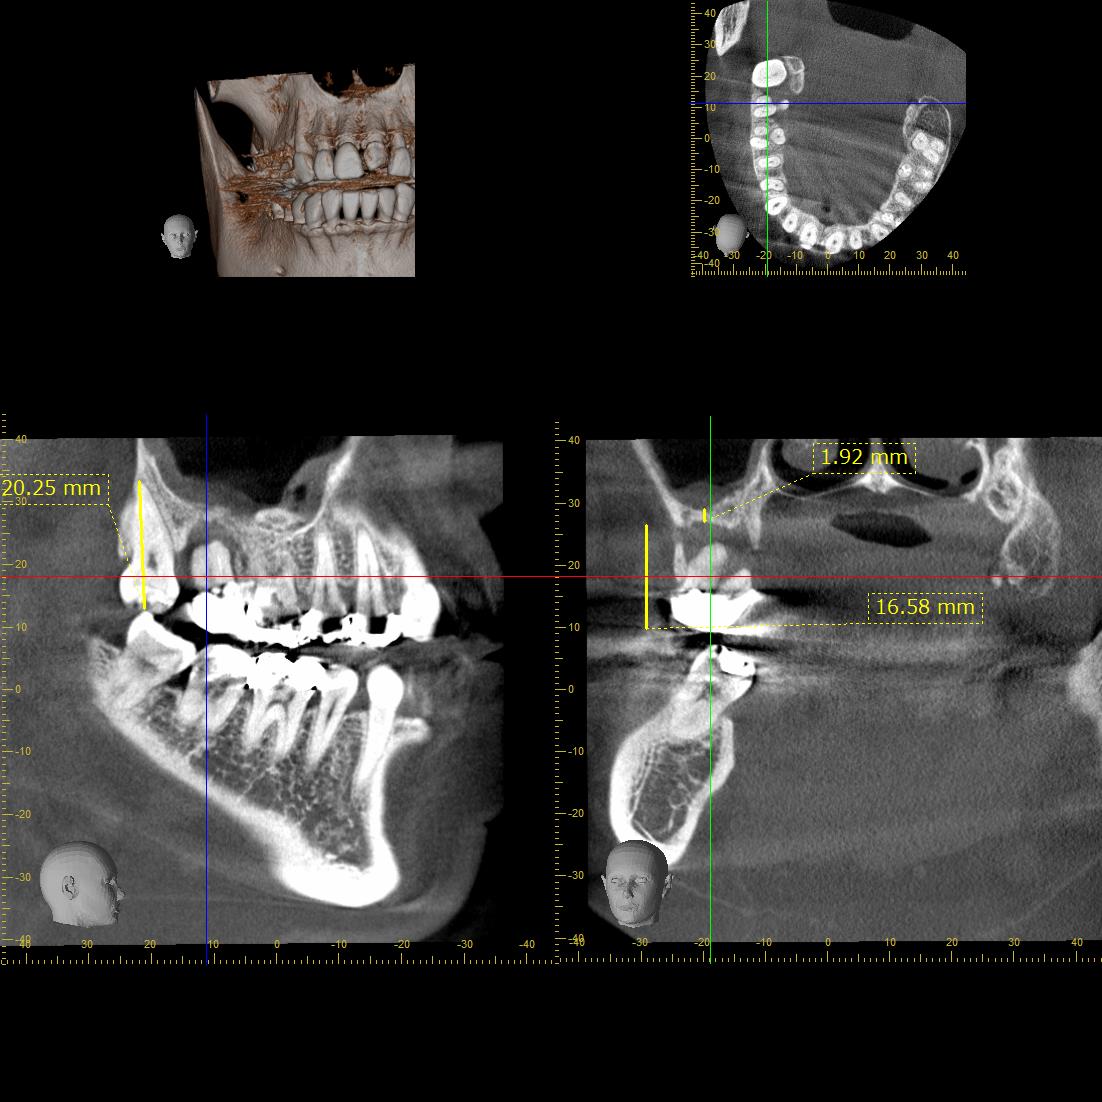

下の写真で左から2番目のクラウンが装着されている歯(第2大臼歯)ですが、デンタルエックス線写真やCTを見ると、根の先まで周囲の骨が吸収しているのが確認できます。

この状態では保存不可能なため、抜歯を行い、その後ろにある親知らずを移植する計画を立てました。

マイクロスコープとピエゾを使用して、上顎洞に穿孔しないように注意しながら受容床の形成を行い、